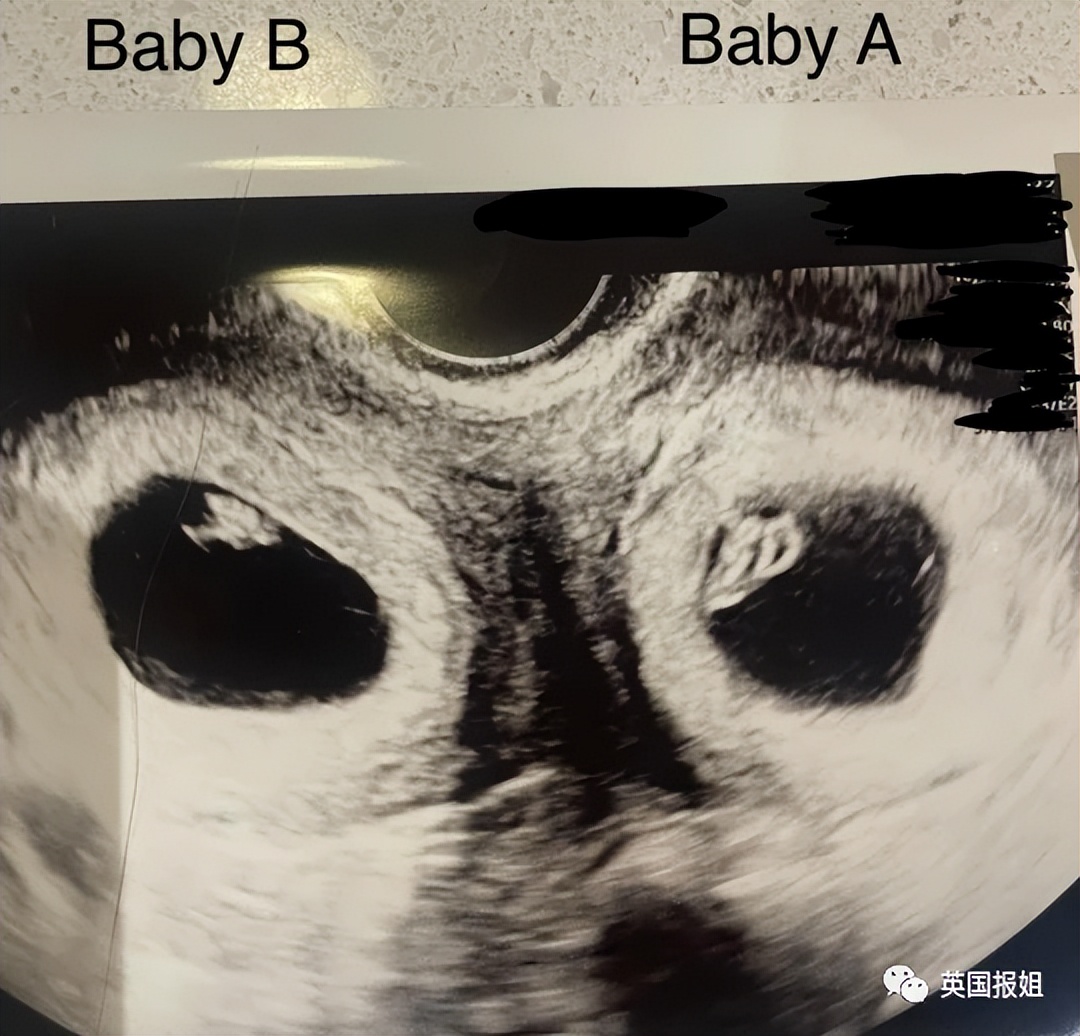

她去做了孕检,第一次听到了孩子的心跳声,雀跃地等着孩子的出生。谁知道,第十周再次孕检时,B超医生突然安静了下来,玛德琳回忆:“我当时慌得不行,生怕有什么情况。”

结果陪在一旁的玛德琳的丈夫挺敏锐,听到好像不止一个心跳声,问医生什么情况。

没想到,玛德琳另一边的子宫也有一个成功着床、体积稍小的胚胎,也已经有了心跳声。她两边的子宫,都怀上了娃:“我吓得目瞪口呆,老公的脸吓得煞白,我以为医生在开玩笑。”